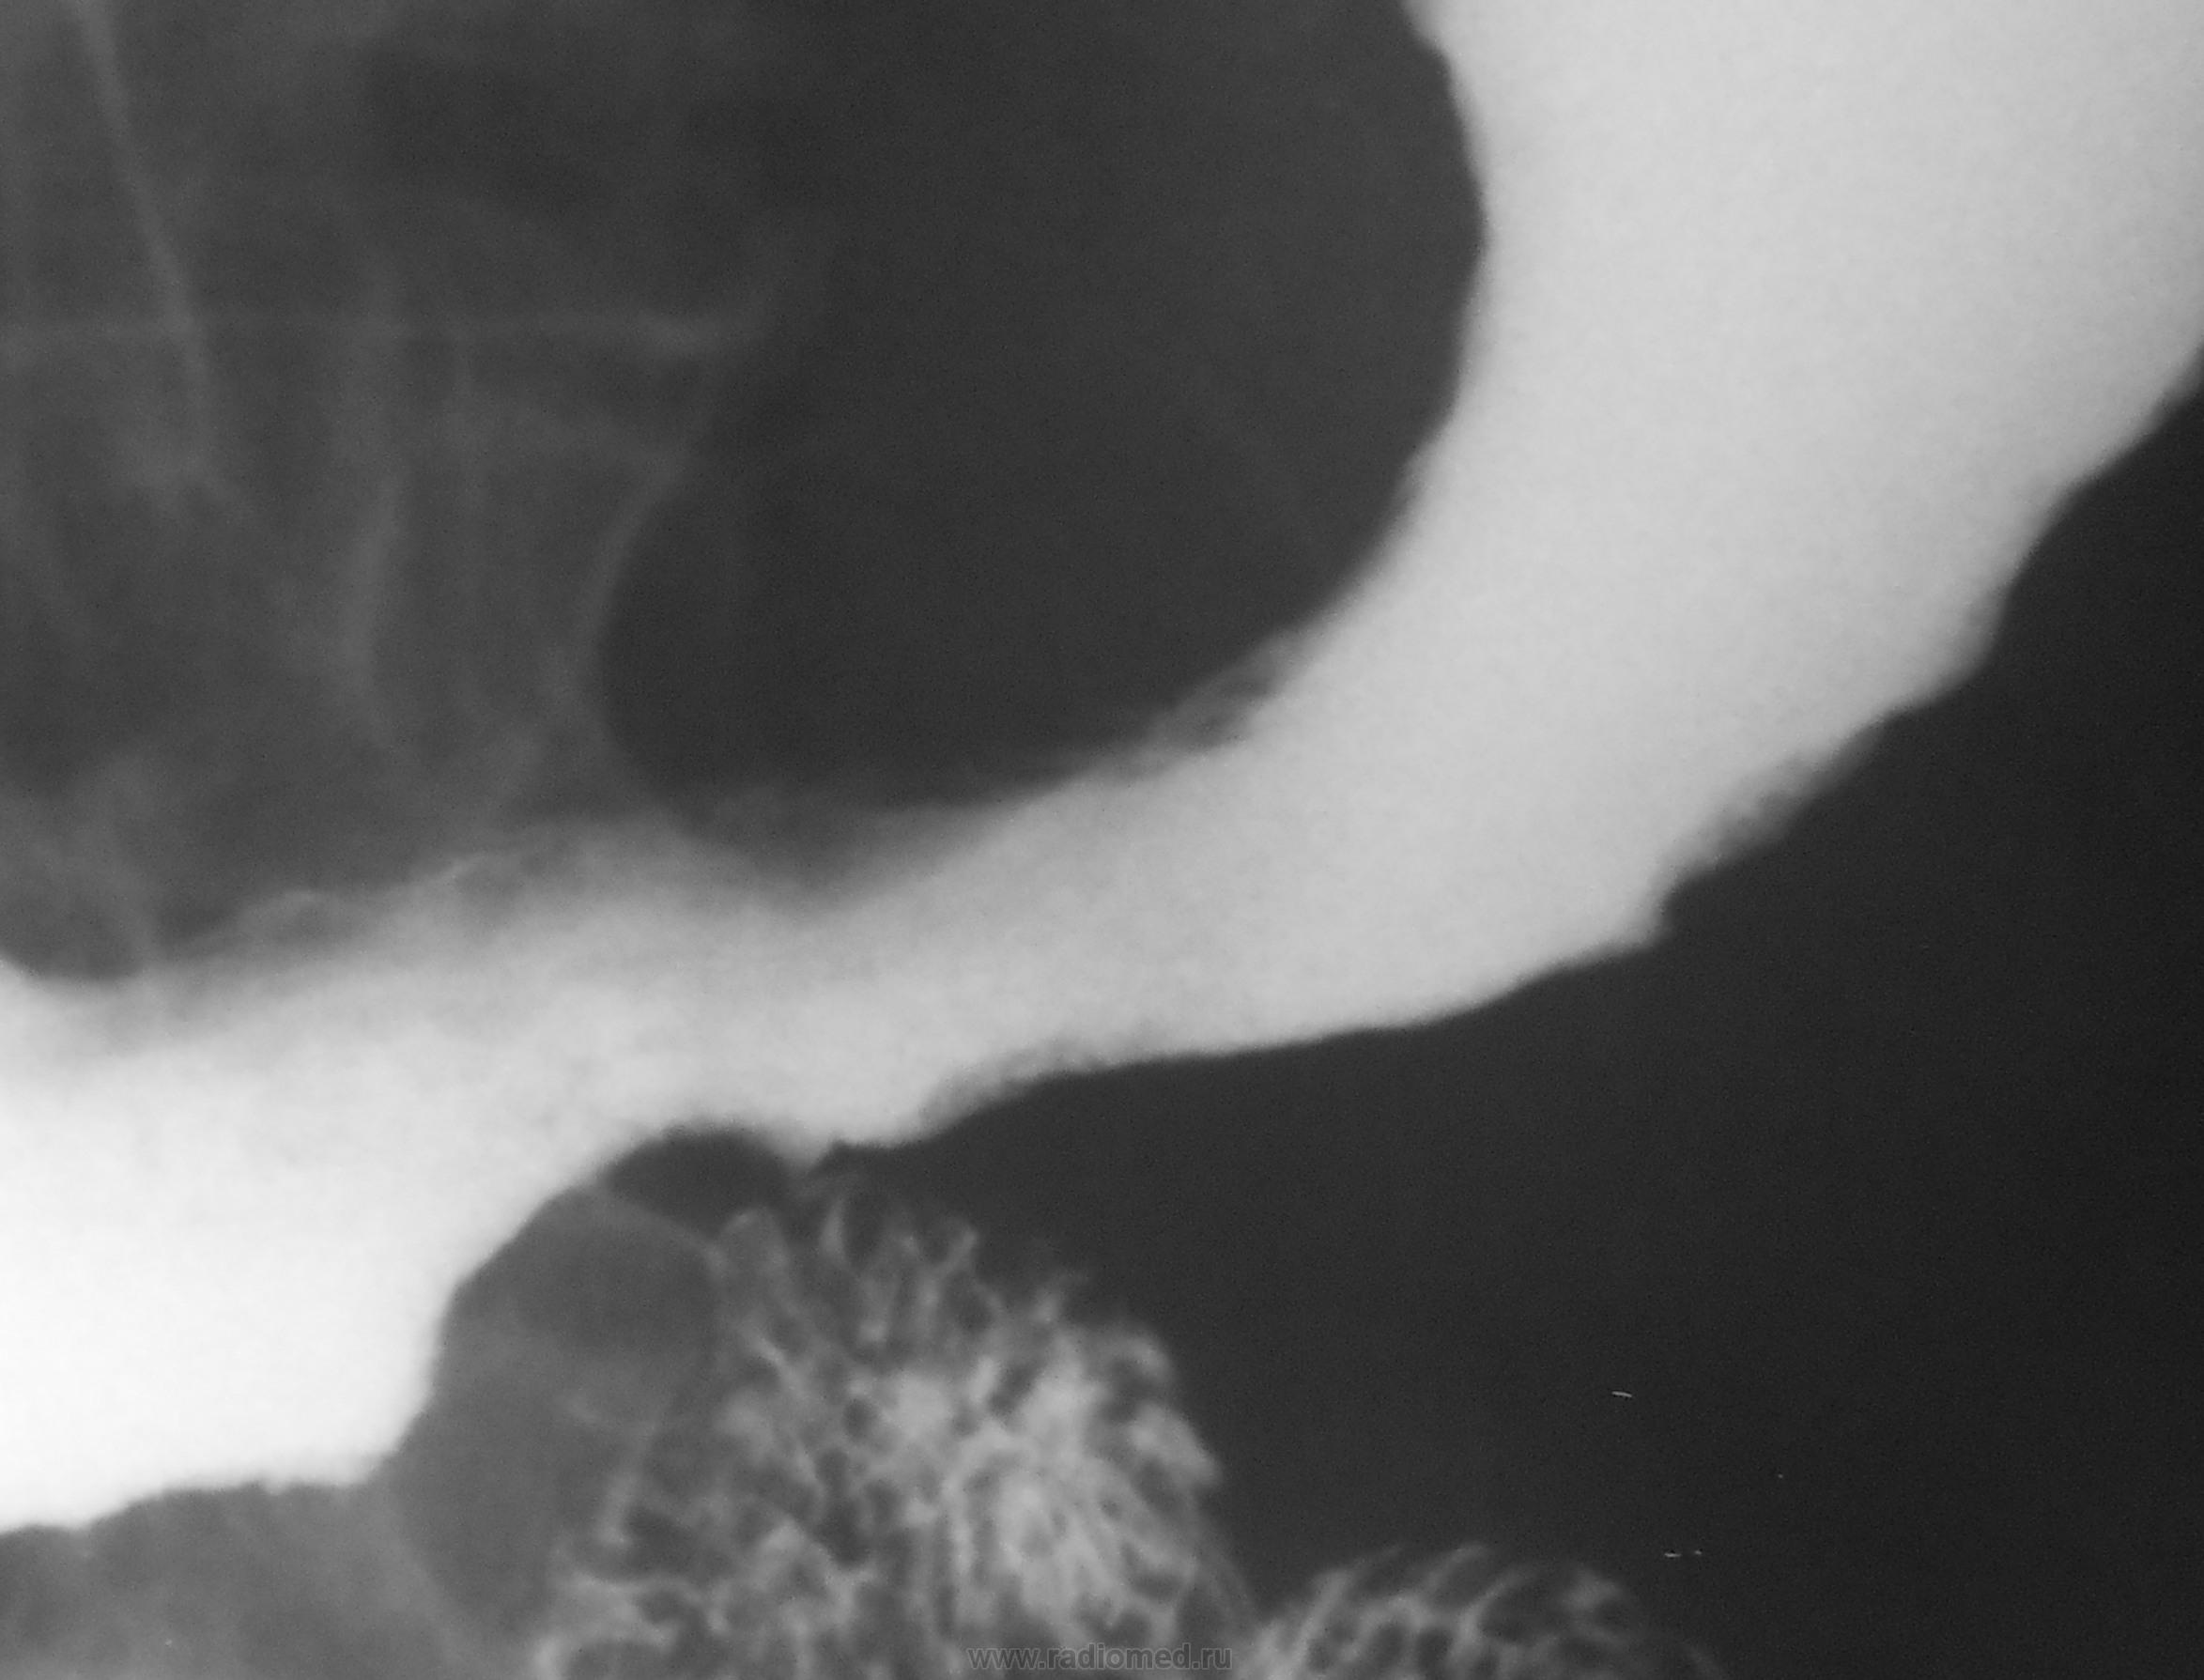

Судя по-всему, поражены отделы от субкардии до антрального.

+ еще дивертикул 12-типерстной кишки.

Конечно, на дивертикул можно было и сделать серию, но в данном, конкретном случае дивертикул не у дел..., при таком распространенном раковом поражении...

Но, отчасти Вы правы, ибо на рентгенологическое исследование пациентка была направлена с диагнозом...- "Дивертикул пищевода".